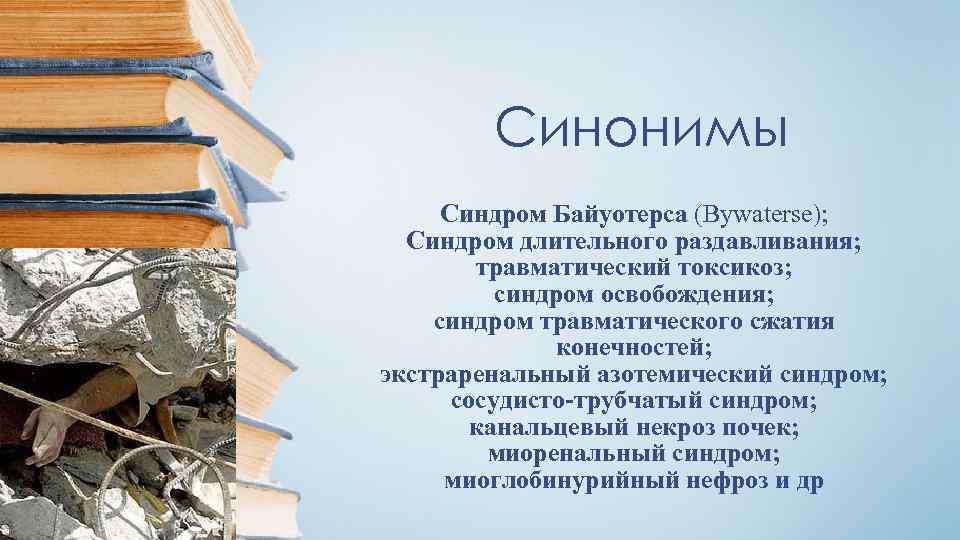

Классификация синдрома длительного раздавливания: основные категории и признаки